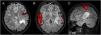

AimsThis work aims to assess the usefulness of functional magnetic resonance imaging (fMRI) in the preoperative study in four patients with DNET. A Philips Intera 3.0 Tesla magnetic resonance imaging scanner and the Blood-Oxygen-Level-Dependent (BOLD) technique were used to obtain the images, making it possible to locate the eloquent areas for language and motor areas through the application of specific paradigms.

ResultsIn one case the tumour was adjacent to Broca’s area, in two cases it coincided with Wernicke’s area, in one patient it was <1 cm from the motor area for the hand and in another close to memory. Only two of the patients were operated on, without postoperative functional deficit. Hemispheric activation contralateral to the tumour suggestive of neuroplasticity was observed in one of the patients.

ConclusionsfMRI is a non-invasive method that allows us to assess the proximity of lesions to eloquent areas, which is key in the evaluation of surgical risk. In addition, it allowed the detection of probable neuroplasticity in one case, which guaranteed the success of the surgery